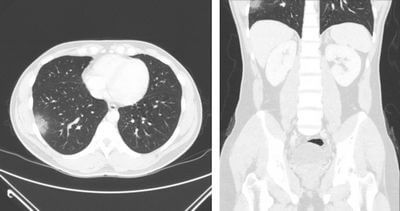

Перш ніж зануритися в деталі того, що можна побачити на КТ-скані, важливо зрозуміти, як працює КТ-сканування. Під час КТ пацієнт лежить на столі, який рухається через машину у формі пончика, що називається комп’ютерним томографом. Сканер використовує рентгенівські промені для створення зображень поперечного перерізу тіла, які потім обробляються комп’ютером для створення детальних 3D-зображень.

Комп’ютерна томографія – це неінвазивний і безболісний спосіб обстеження внутрішніх структур організму. Вони особливо корисні для виявлення патологій у м’яких тканинах, таких як мозок, печінка та легені, які можуть бути невидимими на звичайних рентгенівських знімках.

Комп’ютерна томографія дозволяє отримати багато інформації про внутрішні структури організму. Деякі з речей, які можна побачити на КТ, включають в себе:

Органи

КТ може створювати детальні зображення внутрішніх органів тіла, таких як печінка, нирки, підшлункова залоза та селезінка, що допомагає лікарям діагностувати переломи кісток та пухлини. Це може допомогти лікарям діагностувати широкий спектр захворювань, включаючи рак, інфекції та запалення.